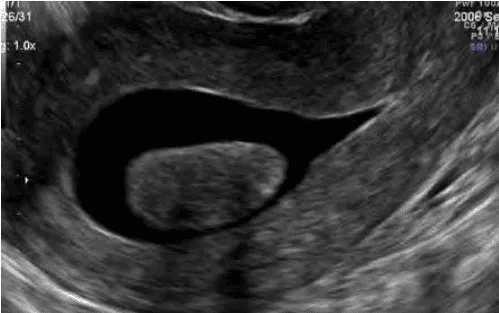

Siêu âm bơm nước: Với u xơ dưới niêm mạc.

Hình ảnh “U xơ tử cung FIGO 0 trên SIS”.

Hình ảnh “Phân biệt polyp và u xơ tử cung FIGO 1 bằng Doppler”.